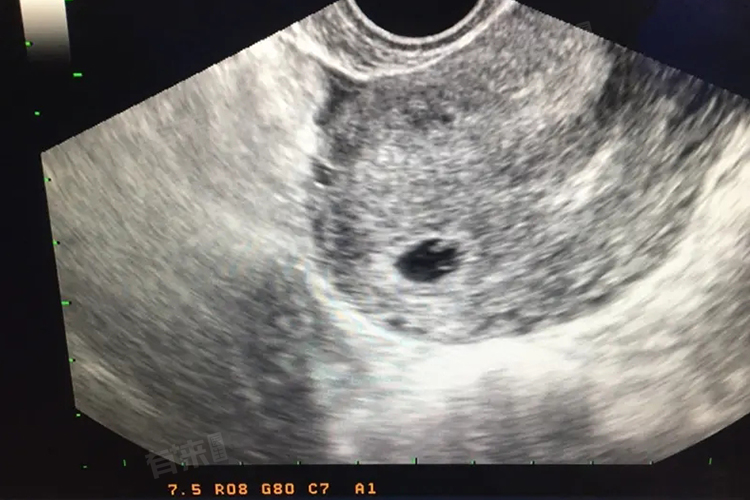

怀孕45天却看不见孕囊,可能由多种因素导致,常见的原因主要包括错误的怀孕日期计算、超声检查技术限制、胚胎发育迟缓、异位妊娠等。

3、胚胎发育迟缓:受精卵质量不佳、孕妇激素水平偏低或存在其他健康问题,都可能导致胚胎发育迟缓。在这种情况下,孕囊的形成和发育速度可能会减慢,导致在怀孕45天时仍无法被超声检测到。

4、异位妊娠:异位妊娠是指受精卵着床在子宫腔以外的部位,如输卵管、卵巢等。由于这些部位无法提供足够的营养支持胚胎发育,因此孕囊可能无法正常形成。在异位妊娠的情况下,宫腔内自然看不到孕囊。此时,孕妇可能会出现腹痛、阴道流血等症状,严重时可危及生命。